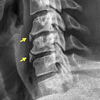

CLAY SHOVELER

- Fracture of the tip of the spinous process of the sixth or seventh cervical vertebra

How well did you know this?